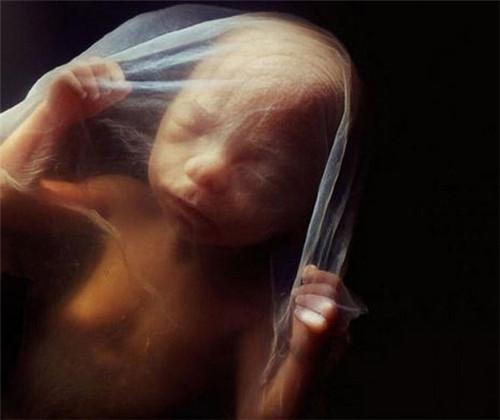

40天,外层胚胎细胞与松散的子宫表层融合,形成胎盘

第8周

第10周。此时眼睑半闭,几周内会完全闭合